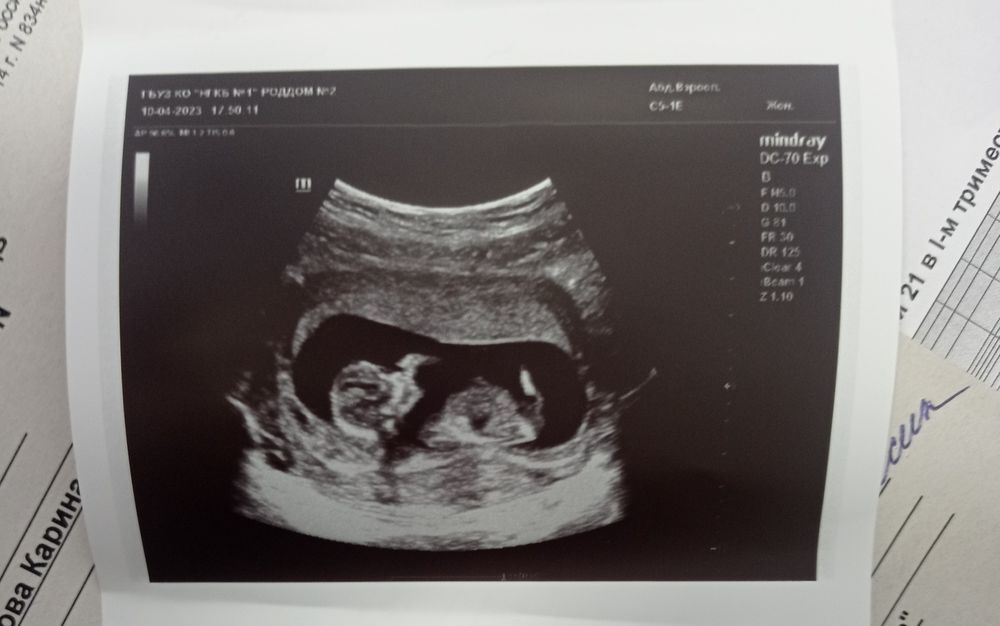

Зачем делают скрининг в 12 недель беременности

Зачем делают скрининг в 12 недель беременности 118 фото